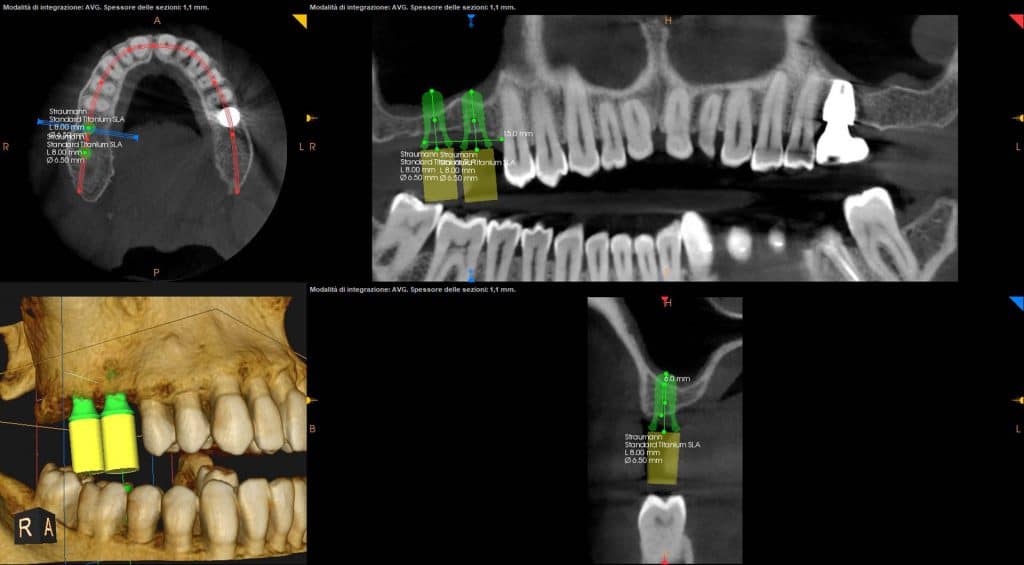

I stopped at about 2 mm from the maxillary sinus floorIn this case, since the distance between the crest and the floor is of about 8 mm in #16 area and 6mm in 17# area, a 6 mm stop is inserted on the first implant and a 4mm stop on the second.

Pre-op and post-op CBCT have been obtained with my Carestream 8100. In addition to providing us with very defined images, this device allows performing CBCT of only three teeth. This greatly reduces the radiation dose for the patient.